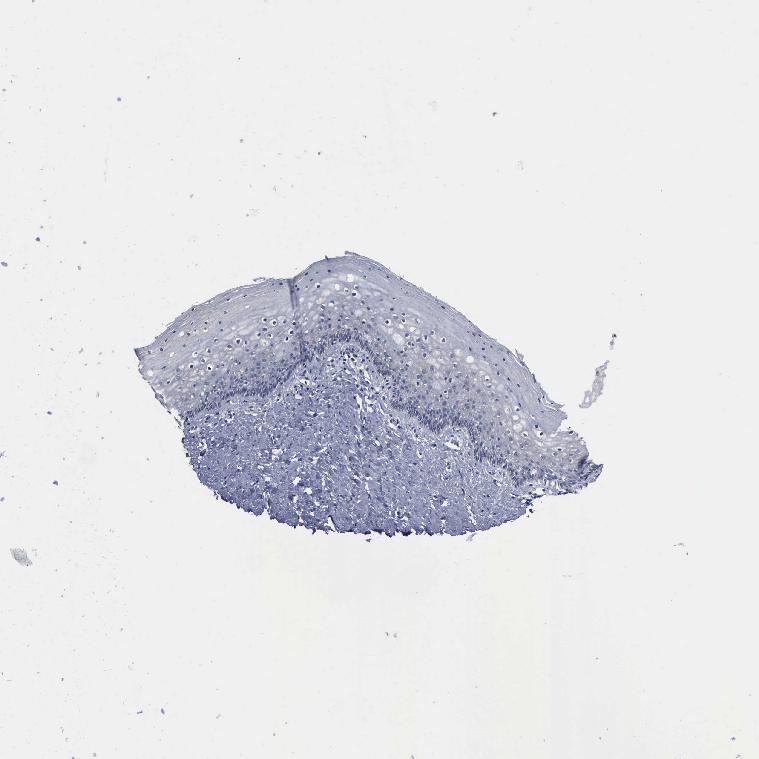

TISSUE PRIMARY DATA VAGINA Show tissue menu

Vagina

VAGINA - Antibody stainingi

Antibody staining in the annotated cell types in the current human tissue is reported as not detected, low, medium, or high, based on conventional immunohistochemistry profiling in selected tissues. This score is based on the combination of the staining intensity and fraction of stained cells.

Each image is clickable and will lead to virtual microscopy that enables deeper exploration of all samples and also displays staining intensity scores, fraction scores and subcellular localization as well as patient and tissue information for each sample.

Antibody HPA000962Antibody HPA004119

Squamous epithelial cells Not detectedNot detected